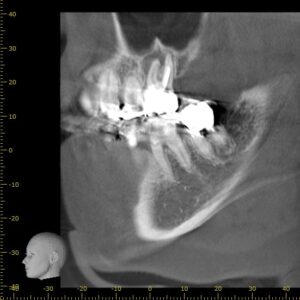

より精確に確認するため、CTを撮影します。

CTが導入されている医院はまだ少なく、インプラントや親知らずの抜歯以外にもレントゲンで分かりづらい根の先端の確認などに力を発揮します。

実際の画像です。

根の周囲が黒く抜けています。

この画像で黒く抜けている部分は菌によって骨が弱くなっている状態です。

このまま放置しておくと病巣が広がり、歯の上方にある副鼻腔に影響を出したり、抜歯になってしまう可能性があります。

また、この根の内部には白く写るはずの根管治療で最後に詰める薬剤が入っていません。

根も曲がっているように見えます。

治療の難易度が高いことが予想できます。